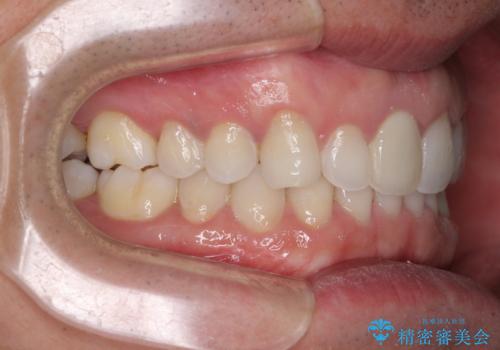

- 口の閉じにくさを気にして来院された患者様です。

患者様と相談の上、横顔の印象から抜歯矯正は必要ないと判断し、IPR(歯と歯の間)並びに歯列全体の後方移動により口元の突出感の改善することとしました。

しっかりと装着時間を守り、ゴムかけも徹底していただいたので、思いの外口元を引っ込めることができました。

これ以上の改善を望まれましたが、非抜歯矯正でこれ以上口元を引っ込めると食いしばりすやすい咬合となるため、この歯列で終了としました。